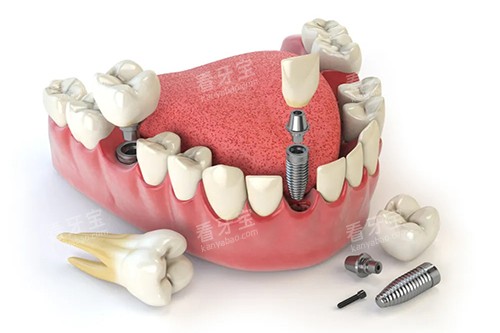

佛山曙光金子口腔掌握了多种可靠的种植技术,如即刻种植技术、all-on-4 种植技术等。

即刻种植技术是在拔牙后立即植入种植体,减少了患者的等待时间,缩短了治疗周期。

all-on-4 种植技术则是通过在上下颌各植入 4 颗种植体,来支撑全口牙修复体,为全口牙缺失的患者提供了一种快速、有效的修复方案。

种植体与牙槽骨紧密结合,能够为牙齿提供稳定的支撑,使牙齿能够正常行使咀嚼功能。

同时,医院选用的种植体材料质量可靠,具有良好的生物相容性和耐腐蚀性,能够确保牙齿的长期使用。